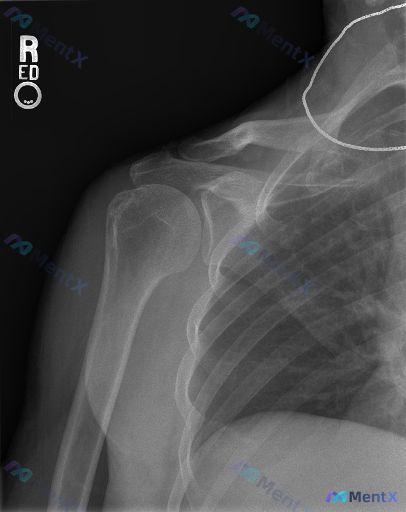

这张右肩X光的大结节毛糙改变,只考虑退变就够了吗?

整理到一份右肩关节正位X光的影像资料,想和大家讨论一下读片思路。

核心影像表现:

- 肱骨大结节区域:皮质密度增高、不规则骨赘形成、形态毛糙,骨小梁结构略显紊乱

- 肩锁关节:轻度间隙变窄、关节面骨质硬化

- 盂肱关节:对合良好,间隙无明显狭窄

- 其余:未见明确骨折、脱位,无明显钙化灶,无恶性骨肿瘤的典型急性征象(如明显骨破坏、骨膜反应)

第一眼可能会想到肩关节退行性改变,或者肩袖相关的骨质反应。但影像描述里特意提到了「形态毛糙」和「骨小梁紊乱」——这两个点,大家觉得只往「退变」上靠够吗?

如果是你接诊,下一步会优先问什么病史、补什么检查?